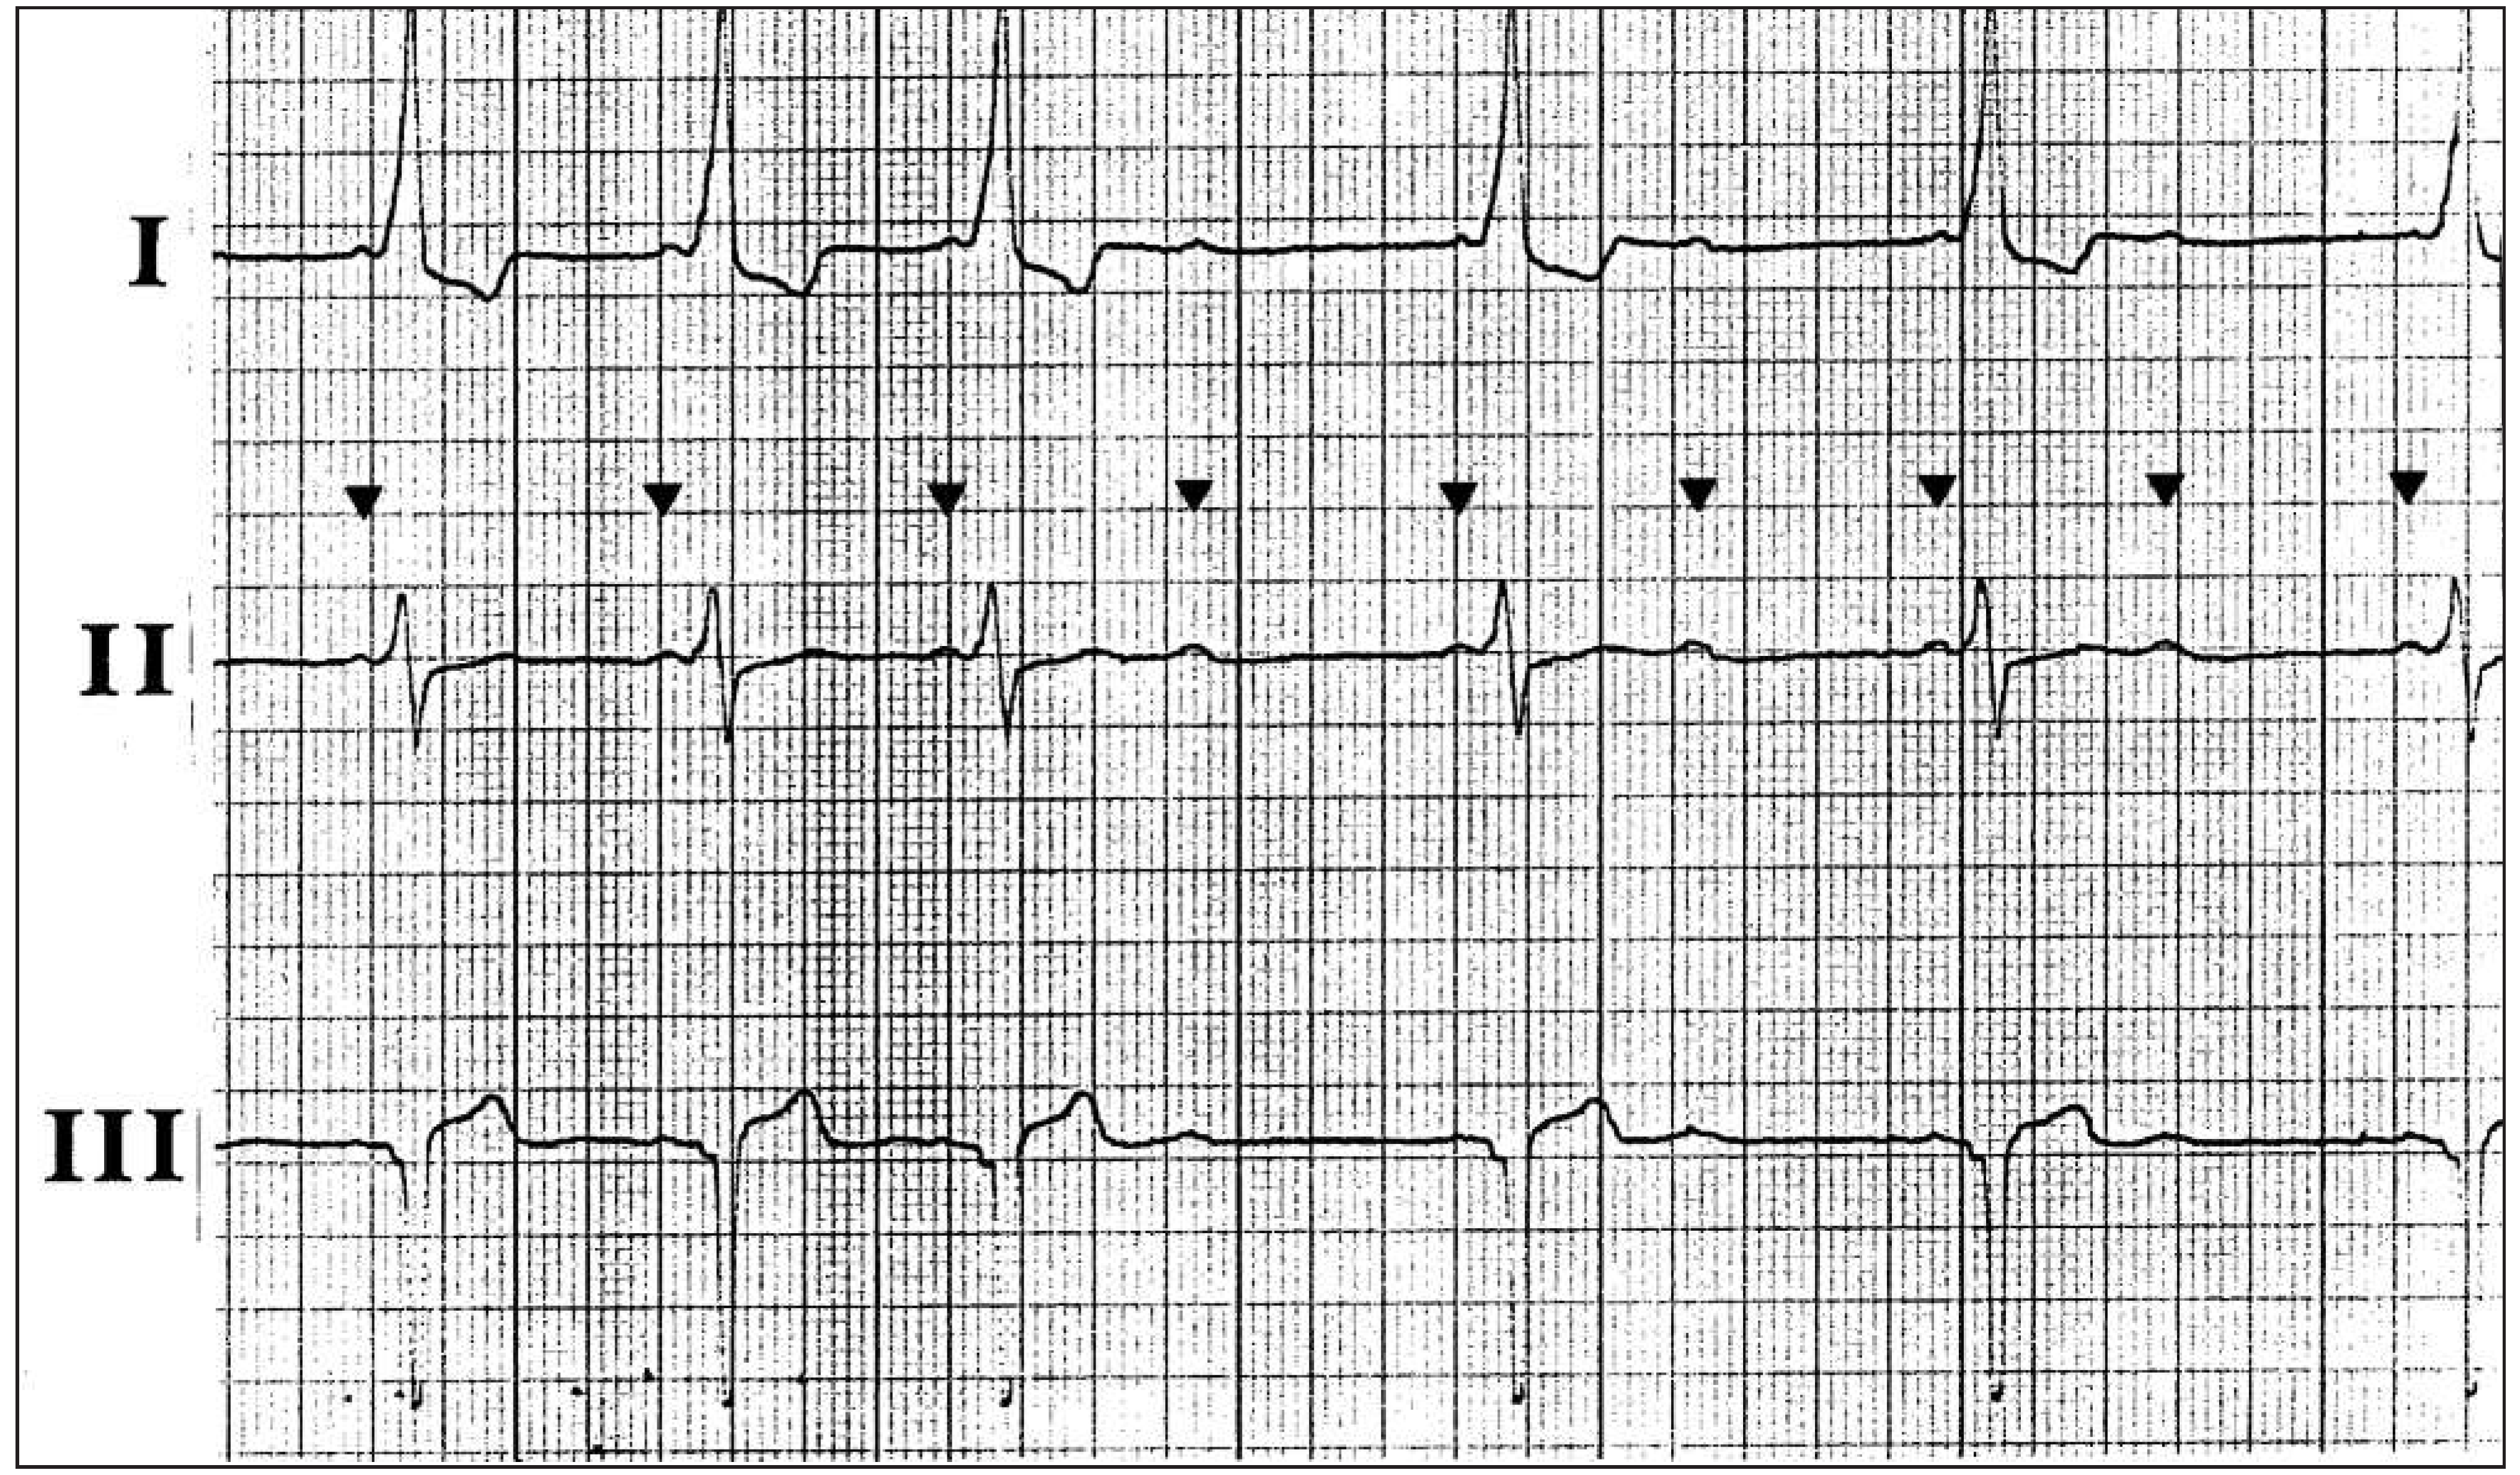

Dyspnoea in a Patient with Alternating Rhythms

1. Case Presentation

2. Questions

- What is your diagnosis?

- What treatment should be proposed?